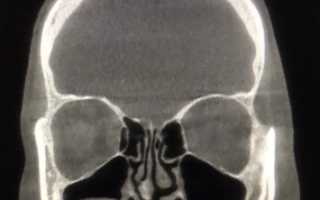

Чтобы поставить правильный диагноз, диагностика гиперпластического синусита должна проводиться посредством сбора полного анамнеза на основании жалоб пациента и проведении объективного осмотра с применением следующих дополнительных методов исследований:

- Рентгенография. Она проводится в трёх проекциях (носоподбородочной, лобно-носовой, боковой) и является наиболее информативным, недорогим и распространённым исследованием.

- КТ и МРТ. Уточняющие диагностические мероприятия, проводимые по большей части в тех случаях, когда у специалиста появляется подозрение на развитие гнойных осложнений болезни.